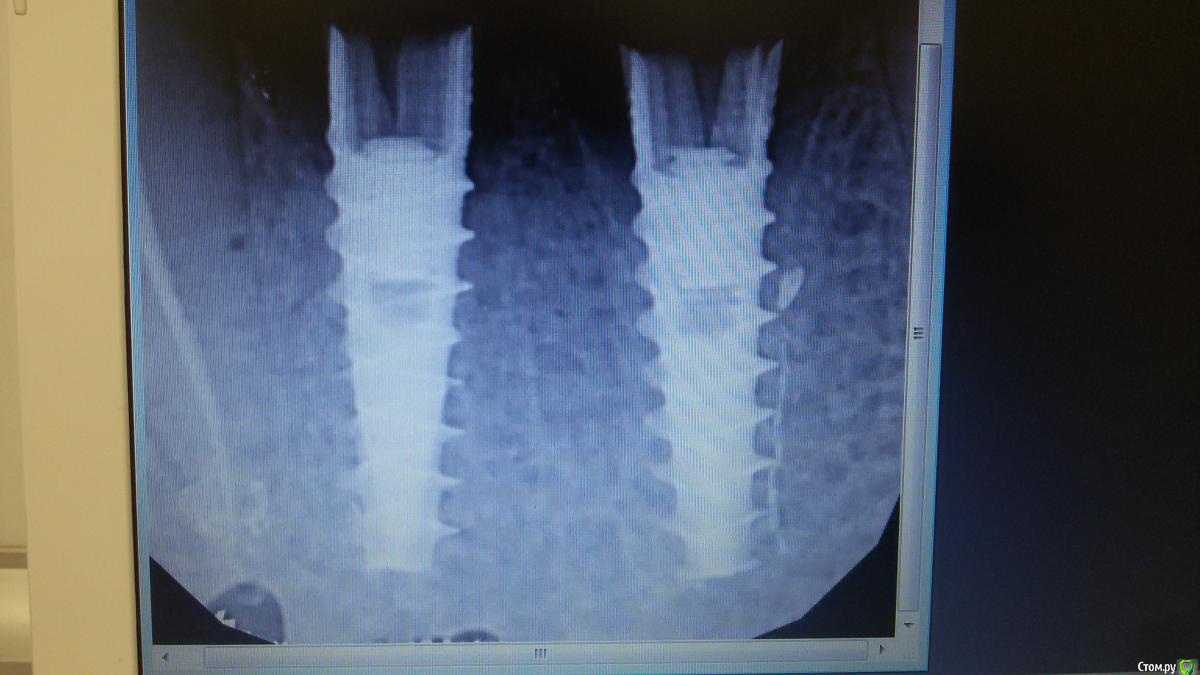

Бандерлога Опубликовано 20 сентября, 2016 Поделиться Опубликовано 20 сентября, 2016 Сломалась ортопедическая конструкция. Имплантаты повреждены, надо удалять. Обломки винтов из шахт достали.1 - Посоветуйте как деликатно удалить имплантаты. 2 - как Вы думаете, какая система? Ссылка на комментарий

kamranchick Опубликовано 20 сентября, 2016 Поделиться Опубликовано 20 сентября, 2016 Хорошо сидят красавцы)) Ссылка на комментарий